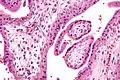

- Micrografía que muestra vellosidades coriónicas. Aumento intermedio. Tinción H&E.